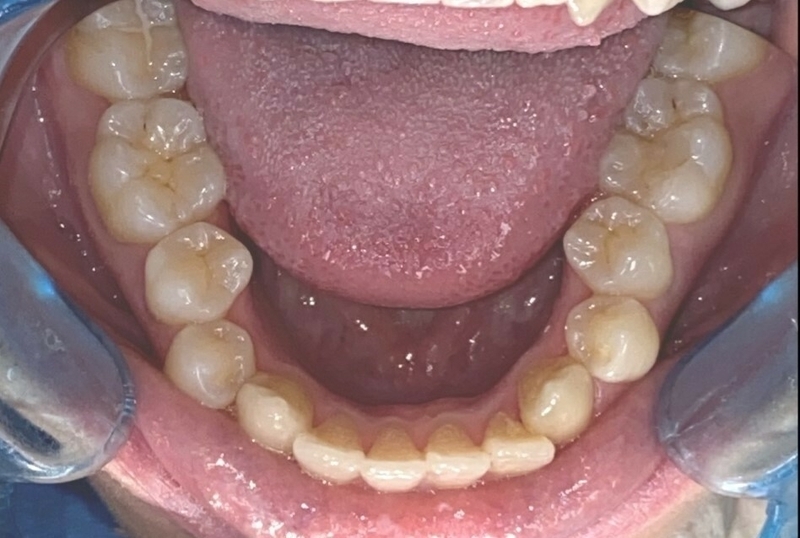

Cas clinique

Cas 1 - Orthodontie par aligneurs invisibles

Avant